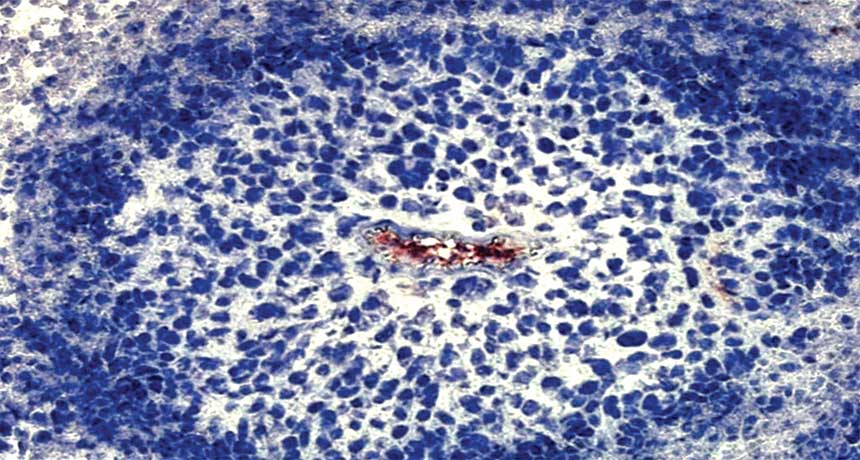

OXYGEN DEPRIVATION Cancer cells (shown in blue) surround a blood vessel (red) in a mouse tumor. Cells on the tumor’s edge are dying, starved of oxygen. But treatments to starve tumors have come up short.

C. Michiels, C. Tellier and O. Feron/Biochimica et Biophysica Acta 2016